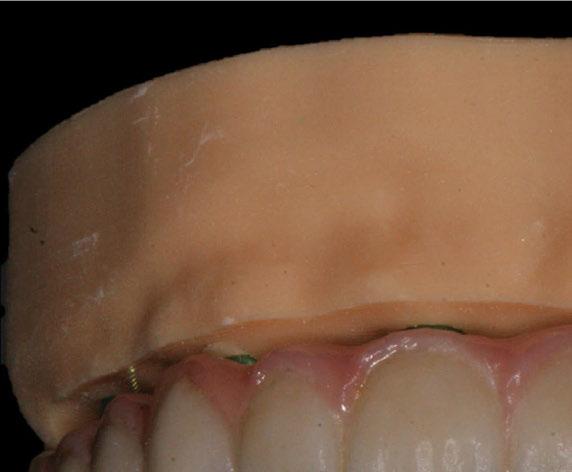

4. Fase protésica provisional

Una vez colocados los pilares provisionales de titanio, se adaptó la férula pick-up modificada y se verificó su correcto asentamiento de los pilares a través de los orificios de ésta. A continuación, se recapturó la férula a los pilares de titanio mediante resina acrílica autopolimerizable (Enamel Temp

Plus®) y, una vez polimerizada, se tomó un registro de mordida, se desatornillaron los pilares y se retiraron de boca. Seguidamente, se atornillaron los análogos verificando que no hubiera movilidad de ningún pilar y se envió al laboratorio para el acabado y pulido final, eliminando todo el soporte y añadiendo un refuerzo metálico por palatino. En boca, se colocaron los tapones de cicatrización de los transepiteliales y se le explicaron las recomendaciones postquirúrgicas y medicación necesaria. Instruimos al laboratorio a dejar los perfiles de emergencia lo más estrechos posibles y los pónticos ovoides entrando unos 3 mm en cada alveolo a fin de preservar la arquitectura gingival presente.

A las 24 horas se citó al paciente nuevamente, se atornilló el provisional en boca y se realizó una

Figura 24. Provisional finalizado tras acabado y pulido en el laboratorio.

Figura 25. Provisional finalizado tras acabado y pulido en el laboratorio.

Figura 26. Entrega del provisional de carga inmediata a las 24 horas.

Figura 27. Ortopantomografía del provisional atornillado en boca para verificar ajuste.

ortopantomografía de verificación del ajuste pasivo de todos los implantes. Por último, tapamos las chimeneas con teflón y resina provisional y se chequeó nuevamente la oclusión, dando nuevamente las instrucciones de higiene y mantenimiento de la prótesis provisional (Figuras 24-27).